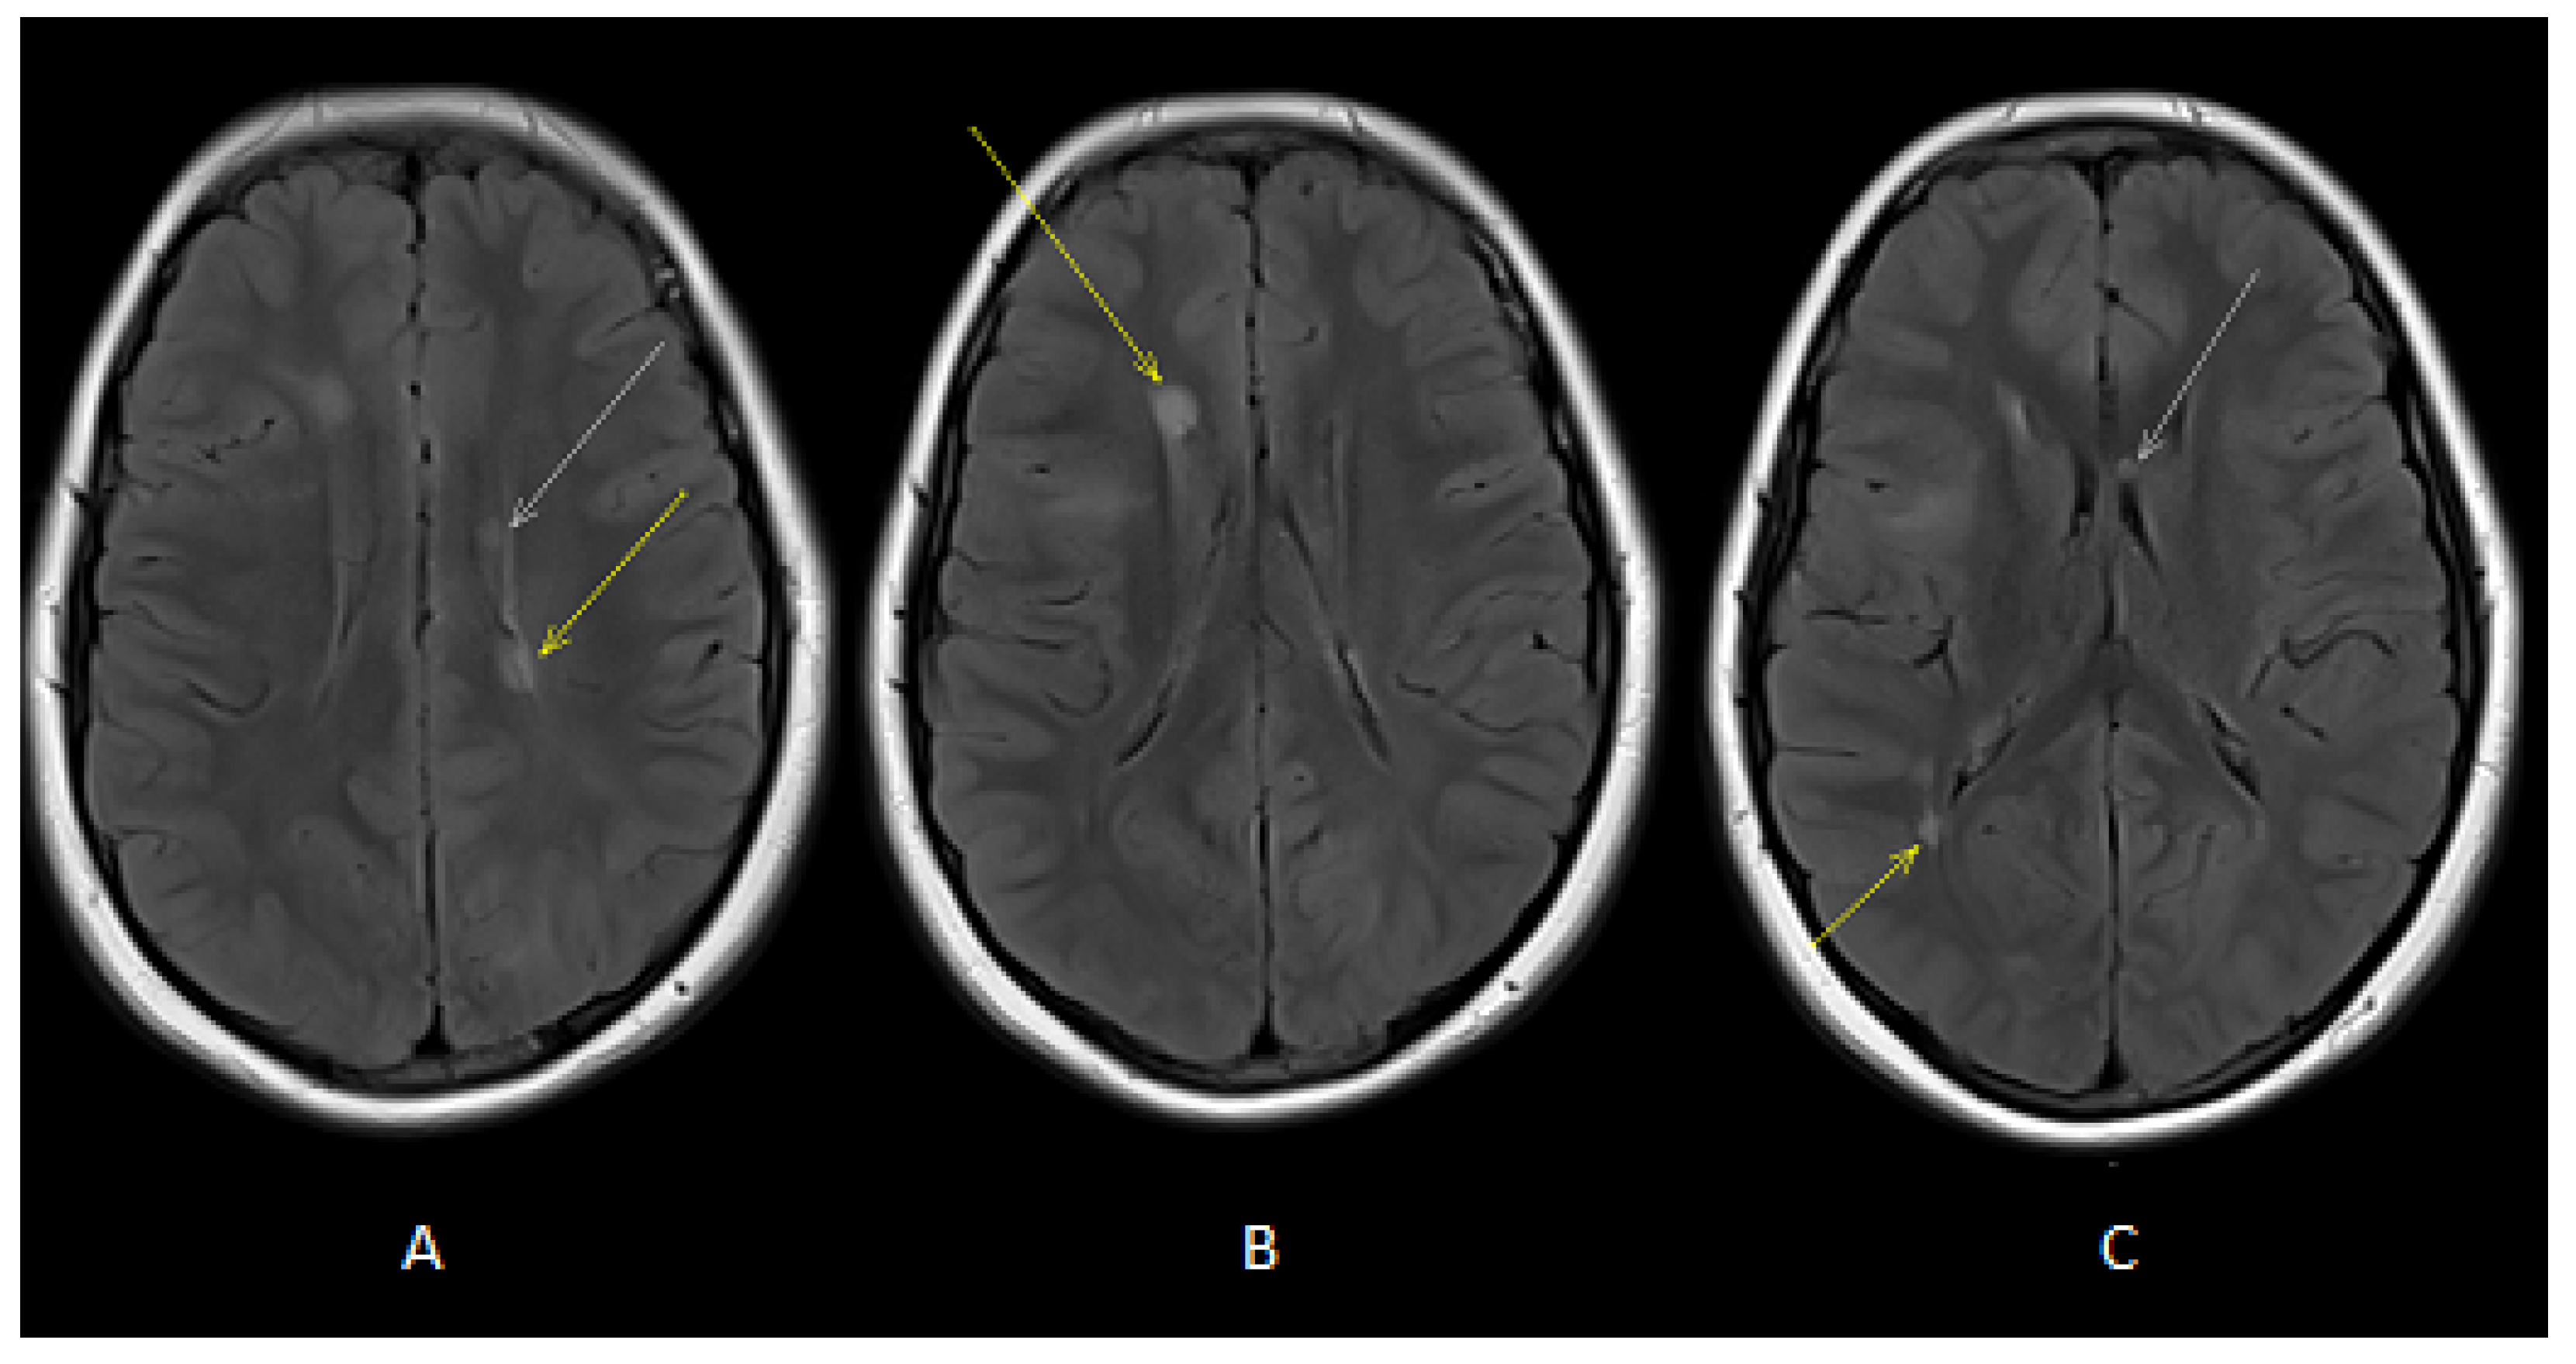

Figure 2.

Axial T2-FLAIR images (A,B) showed oval-shaped lesions in deep periventricular white matter of both cerebral hemispheres (white and yellow arrows). Axial T2-FLAIR image (C) showed oval-shaped lesions in deep periventricular white matter (yellow arrow) and in the corpus callosum (white arrow).